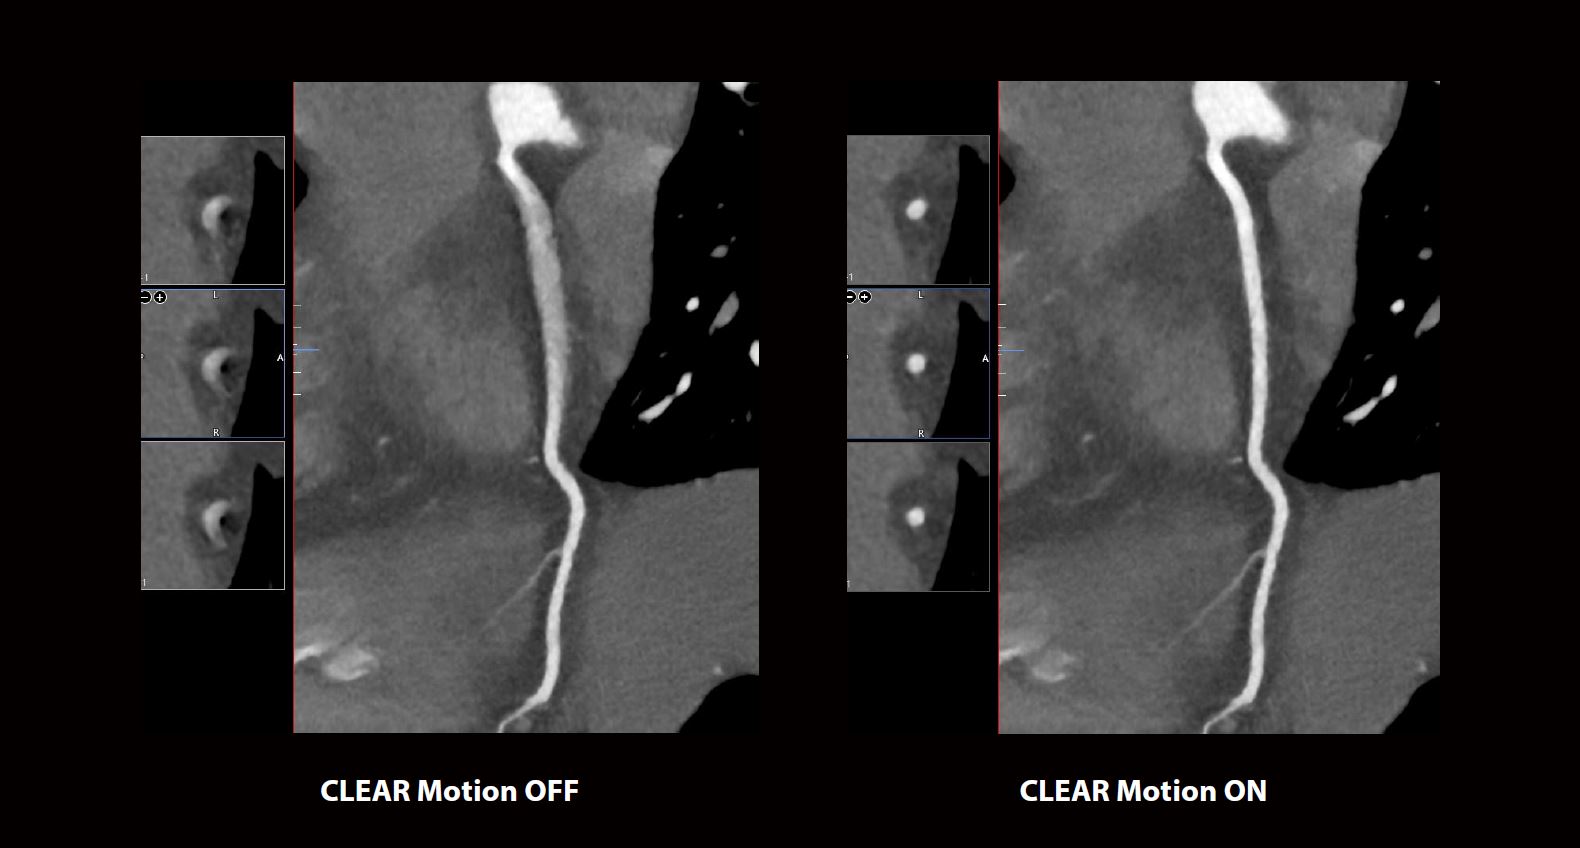

Зображення (ліворуч) середньої частини правої коронарної артерії (ПКА) демонстрували значні артефакти руху, що робило сканування недіагностичним. Завдяки використанню технології CLEAR Motion (праворуч) артефакти руху були ефективно мінімізовані. Зображення CLEAR Motion дозволили провести діагностичну оцінку якості ПКА, підтвердивши відсутність захворювання коронарних артерій.

CLEAR Motion Cardiac розраховує диференційний рух у просторі проекції з часовою роздільною здатністю 14 мс для створення точної карти вектора руху, яка коригує рух під час реконструкції зображення. Як показано в цьому прикладі, CLEAR Motion Cardiac особливо ефективна для забезпечення діагностичної якості сканування. Усунувши рух в ПКА, вдалося уникнути повторного сканування, заощадивши контраст і дозу опромінення для пацієнта, забезпечивши при цьому ефективний догляд за пацієнтом.